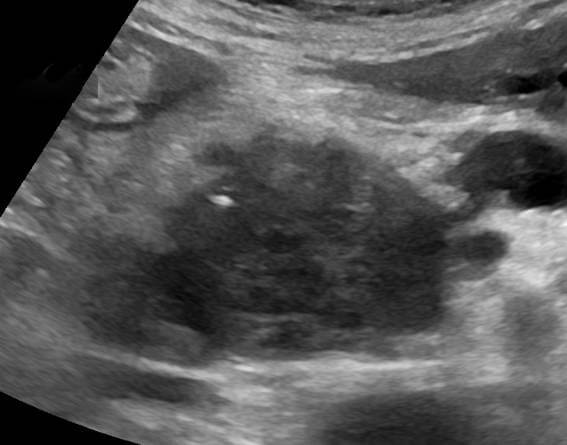

Dr. Hamer worked at a cancer clinic and asked thousands of patients about their experiences. He found out that everyone had some trauma before their cancer growth. Hamer was able to interview and do Ct-scans of thousands of cancer patients.

After he gathered all the data, he made a remarkable discovery. Hamer found a white spot on CT-scans of every cancer patient. Patients with a similar diagnosis had this concentric ring in the same place on the CT-scan.